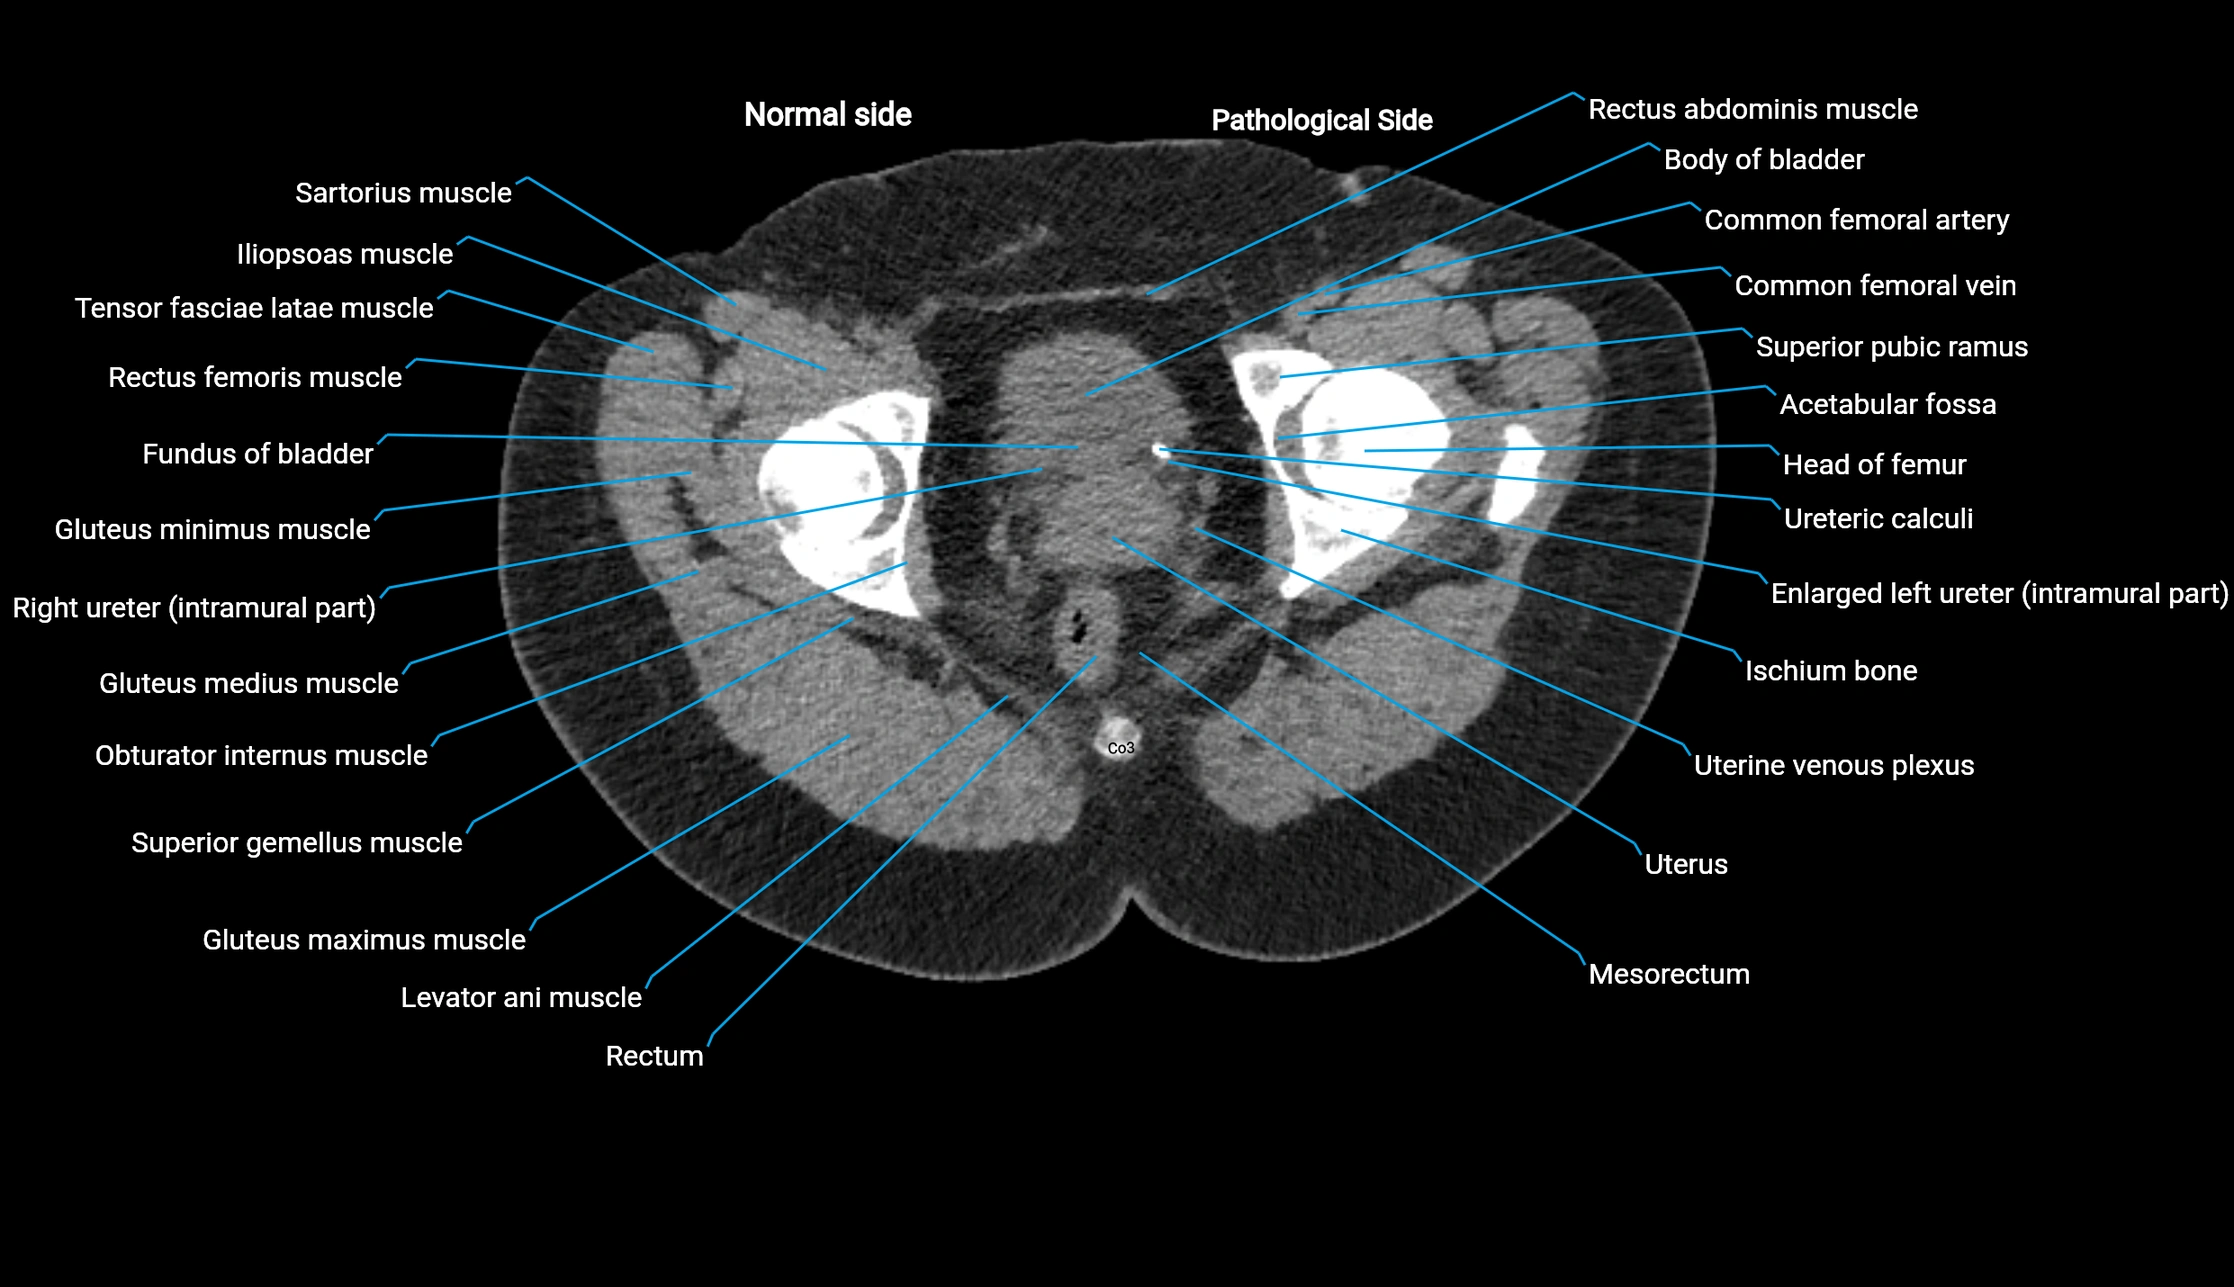

CT image

image